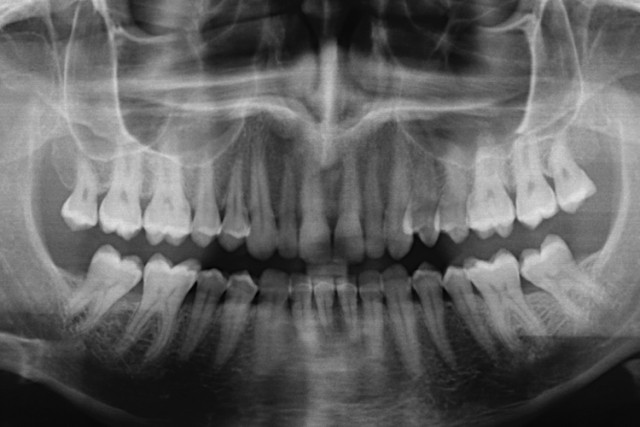

Dental amalgam is made up of 50 percent mercury - a toxic heavy metal linked scientifically to neurological problems, kidney problems and infertility. In 1991, the World Health Organization reported that mercury fillings are the predominant cause of mercury exposure. So, the question remains: is YOUR dentist telling you the whole truth about your health? The American Dental Association (ADA) continues to deny the dangers of mercury-based, silver fillings - insisting that dental amalgam is a “safe, affordable and durable” material used to restore the teeth of over 100 million Americans. It’s time to expose the real health threats posed by modern dentistry. On the next NaturalHealth365 Talk Hour, Jonathan Landsman and David Kennedy, DDS, a biological dentist and noted authority on the dangers of modern dentistry, reveal the shocking hazards of mercury-based silver fillings, fluoride treatments, root canals plus much more! If you would like to discover the best ways to avoid being harmed by these toxic dental practices, join us for an important program that the ADA would wish you to miss. To hear this FREE show – visit http://www.naturalhealth365.com/free-shows and enter your email address for show details.

If mercury stayed inside teeth, as intended, the danger might not be so severe. But the fact is: silver fillings leak mercury daily in the form of invisible and odorless vapors - which are released with such common, everyday activities as chewing food, drinking hot beverages, grinding teeth and undergoing routine dental procedures. In a video produced by the International Academy of Oral Medicine and Toxicology, an extracted tooth displayed against a phosphorescent screen clearly shows streams of vapor issuing forth. According to the IAOMT, the vapor is being released in amounts 1,000 times higher than the EPA limit for the air we breathe. Animal studies have shown that mercury fillings cause accumulations of the heavy metal in the jaw, stomach, liver and kidneys - and can spread to every organ in the body. Researchers also found decreases in kidney function - and noted, alarmingly, that mercury migrates to the placenta and fetus as well. In addition, an often-fatal heart condition, idiopathic dilated cardiomyopathy, has been linked to mercury. The hearts of patients with IDCM have been shown to contain 22,000 times more mercury than hearts that are affected by ordinary cardiovascular disease. Harold Loe, former director of the National Institute of Dental Research, reports that using mercury requires removing large amounts of healthy tooth substance along with the diseased areas, resulting in a weakened tooth. The tooth may eventually break off, necessitating a crown - which also may break down, leading to costly repairs and, eventually, total failure and extraction. Join us, for the next NaturalHealth365 Talk Hour, to find out how to minimize the harm from these dental dangers including, how to find a biological dentist, tips on safe mercury filling removal, and more. To hear this FREE show – visit http://www.naturalhealth365.com/free-shows and enter your email address for show details.